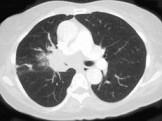

问题 男,56岁,咳嗽,咯血1月余,有吸烟史30余年,结合CT检查图,选出最可能的诊断 ( )

选项 A.肺结核 B.肺炎 C.结节病 D.肺错构瘤 E.中央型肺癌

答案 E